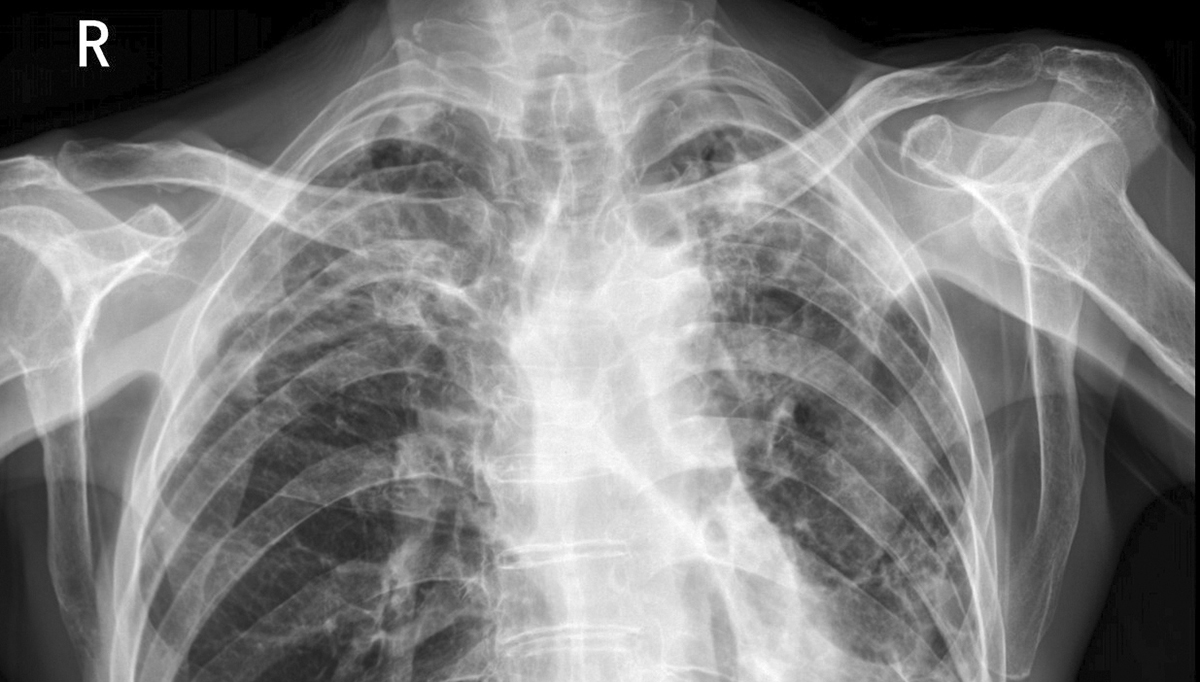

高分辨率与灰阶表现:医用影像显示器普遍采用 1000 万像素以上的超高分辨率(如 3MP、5MP、8MP),可清晰呈现 CT、MRI 等影像的细微结构(如肺部小结节、脑部微小出血点)。同时支持 14 位(16384 级)以上灰阶,精准区分组织密度差异,避免漏诊。

DICOM 标准校准:医用影像显示器内置 DICOM Part 14 灰度标准显示函数,确保不同设备、不同时间显示的影像亮度、对比度一致,符合临床诊断规范性要求。